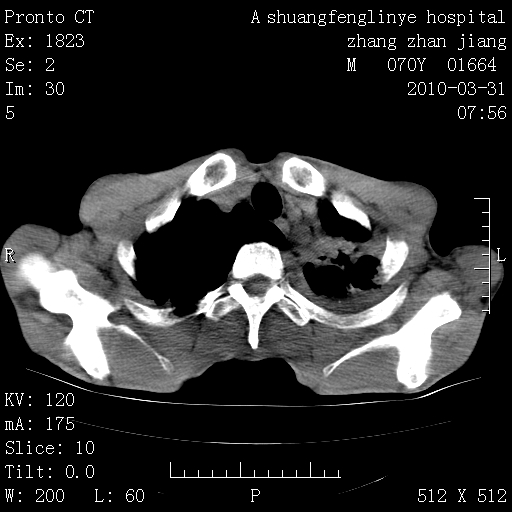

双上肺继发型tb并左上空洞形成,主动脉冠脉钙化。

1)两肺上叶继发性肺结核并左肺上叶空洞形成。2)冠状动脉及主动脉钙化。